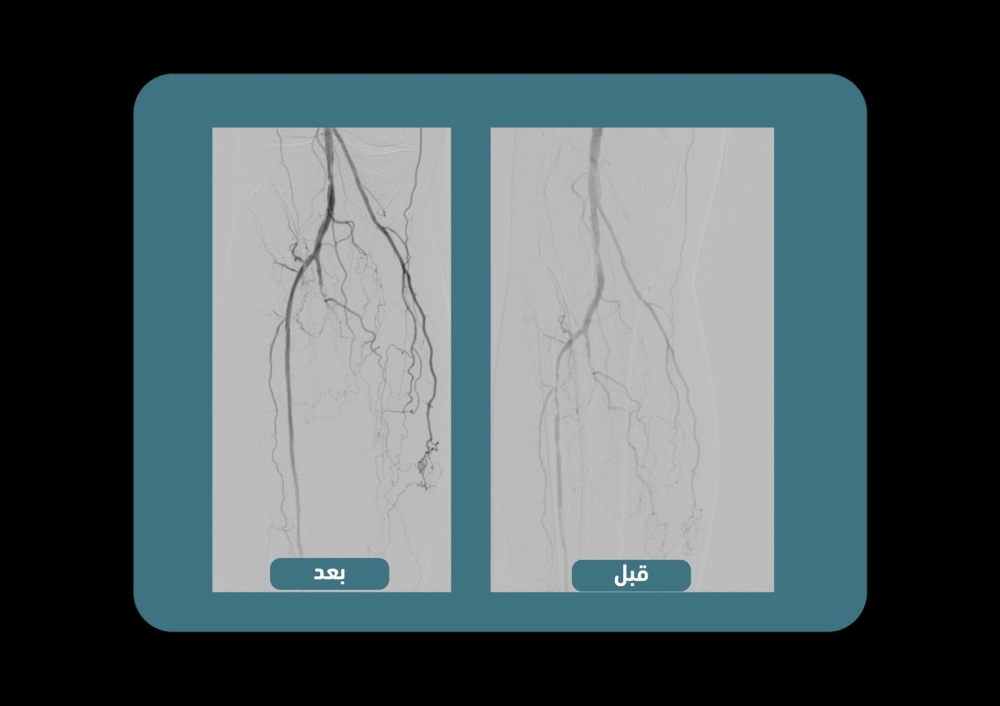

بدأت الخدمة بنجاح مع علاج أول حالة بواسطة فريق الأشعة التداخلية، الذي يتكون من مجموعة من الأطباء الاستشاريين. أوضحت المدينة أن إجراءات الأشعة التداخلية تعتبر تقنية معترف بها عالمياً لعلاج انسدادات الشرايين الطرفية، بمعدلات نجاح مرتفعة وبأمان كبير.

العملية تتم عادةً في اليوم نفسه باستخدام تخدير موضعي، مما يتجنب الحاجة للتنويم. يتم تحديد المرضى المؤهلين بعد تقييمهم من قبل أطباء الجراحة العامة أو قسم الغدد الصماء، ثم يُحولون لعيادة الأشعة التداخلية لإجراء الفحوصات اللازمة. بعد ذلك، يتم تحديد العلاج المناسب ومعالجة المريض عبر عملية القسطرة التي تُجرى في نفس اليوم، مع ضمان خروجه بعد التأكد من سلامته.